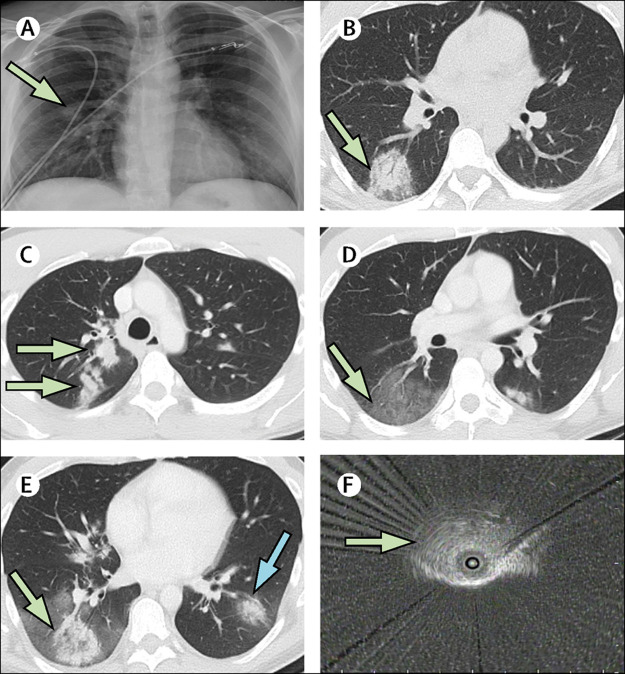

Figure 1.

Imaging with chest radiograph, chest CT, and radial EBUS

(A) Admission chest radiograph (hospital day 1) with right mid-lung nodule (arrow). (B) First chest CT (day 2) with right lower lobe rounded opacity with possible halo sign (arrow). A second chest CT (day 6) showed new right upper lobe nodular opacities (C; arrows), a new large ground glass opacity in the right lower lobe (D; arrow); and enlargement of the right lower lobe rounded opacity with possible reverse halo sign (E; green arrow) and a new left lower lobe rounded opacity (E; blue arrow). (F) Radial EBUS image of right lower lobe rounded opacity (arrow) used to target the transbronchial lung biopsy on day 9. EBUS=endobronchial ultrasound.

On hospital day 2, CT of the chest found a rounded opacity in the right lower lobe (figure 1B); the remainder of the lungs appeared normal. On day 4, the patient's peak temperature was 37·8°C, and his cough and dyspnoea had improved; intravenous azithromycin was stopped. On day 5, fever to a peak of 38·9°C occurred, and the patient developed rigors and severe coughing. Intravenous azithromycin (500 mg once a day) was restarted and oral clindamycin (300 mg once every 6 h) was administered, without clinical improvement. A repeat chest CT on day 6 showed enlargement of the right lower lobe opacity, which had become surrounded by a large new ground glass opacity. A new rounded opacity was present in the left lower lobe, and a new multilobulated opacity in the right upper lobe (figure 1C–E). The CT report suggested atypical pneumonia of fungal or viral origin. A repeat RT-PCR of an NP swab for SARS-CoV-2 was negative on day 7. Severe cough, malaise, rigors, and fever continued, and oxygen saturation was 92–94% at ambient air. Antibiotics were stopped on day 8, and prednisone 40 mg was given orally on the mornings of day 8 and day 9 for presumed cryptogenic organising pneumonia. Consulting radiologists noted CT evidence of a halo sign and reverse halo sign (figure 1B and 1E),7 suggestive of invasive fungal infection and not characteristic of previously reported CT findings for COVID-19.1, 8 On day 8, a serum galactomannan assay was ordered and pulmonary consultation was requested. The pulmonary consultant recommended bronchoscopy with transbronchial biopsy and BAL. Given the epidemic of COVID-19 in New York City at the time, the pulmonary team still considered COVID-19 a possible cause of the pulmonary disease.

On hospital day 9, bronchoscopy was done with appropriate personal and environmental protection precautions for COVID-19, including intubation. The airways appeared normal without inflammation or secretions. The original right lower lobe opacity was targeted for biopsy, and radial endobronchial ultrasound was used to select the airways leading directly to the lesion (figure 1F). Transbronchial lung biopsy and BAL were done in the right lower lobe lateral segment through the target airways. Appropriate specimens were sent for histopathological and cytological examinations and for routine bacterial, fungal, and mycobacterial cultures, and a BAL galactomannan assay. Validated testing of BAL for SARS-CoV-2 was unavailable, and thus a swab used for NP specimens was swirled in the BAL specimen and sent for RT-PCR.